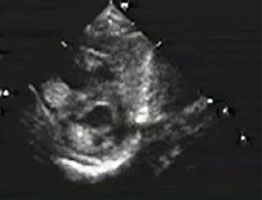

9、日齢15の新生児。呼吸障害と経皮的酸素飽和度の軽度低下を認め3日前から増悪した。心エコー図を示す。この症例で誤っているのはどれか。2つ選べ。

- 心拡大をきたす。

- 下大静脈が拡大する。

- 垂直静脈が下行している。

- 心房間交通は左右短絡である。

- 四腔断面像は新生児遷延性肺高血圧症と類似する。

正解:a, d